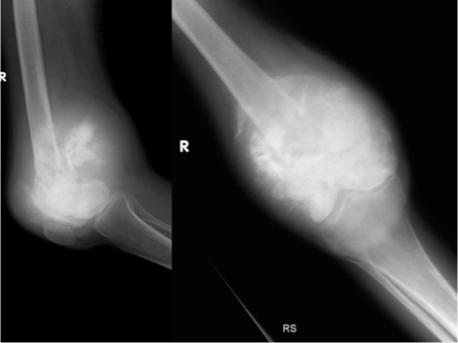

A 12-year-old boy presents to the pediatric emergency department with pain in his right lower extremity.

He was recently playing in soccer, but he denies any trauma to the leg.

Physical examination is notable for mild swelling in the right mid-tibia and tenderness to palpation.

A radiograph of the leg demonstrate periosteal elevation and "onion skinning" concerning for malignancy.

Ewing sarcoma